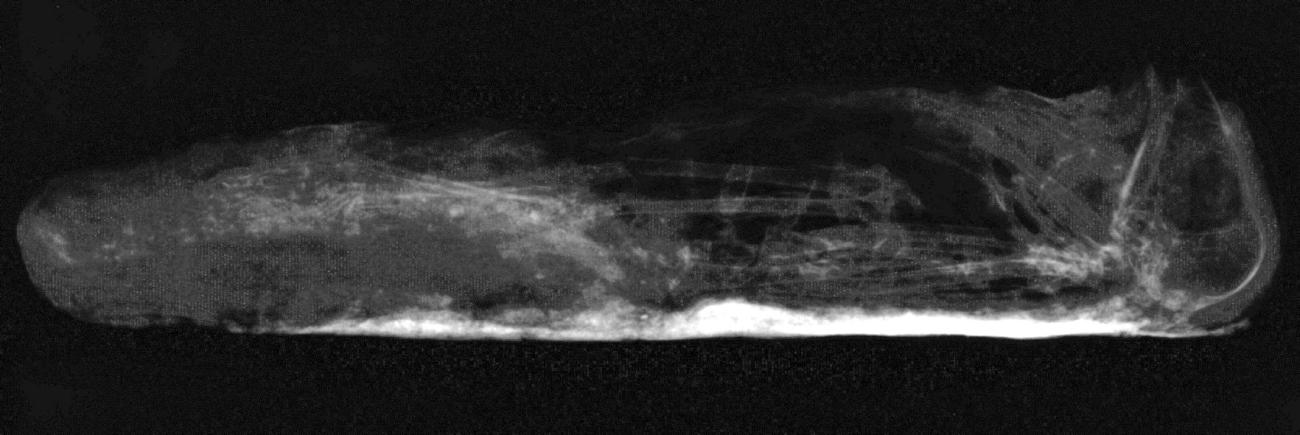

A lack of evisceration was observed (McKnight and Atherton in press) with several complete and articulated bird mummies identified as small birds of prey, mostly Falco tinnunculus (Kestrel) and Accipiter nisus (Sparrowhawk). The internal organs were thought to have become dehydrated and, as a result, had decreased in size within the abdominal cavity, and appeared as radiopaque shadows on radiographic images (See Figure 2).

Anointment methods, attributed to resinous substances that adhered to the bird during mummification, were observed as radiodense areas. These were visible in different ways: as a complete coating around the corpse (see Figure 3); or in patches, indicative of the resin1 settling in a particular area, synonymous with the final resting position, within the wrappings before becoming completely dry (Atherton 2012; McKnight 2010) (See Figure 4).